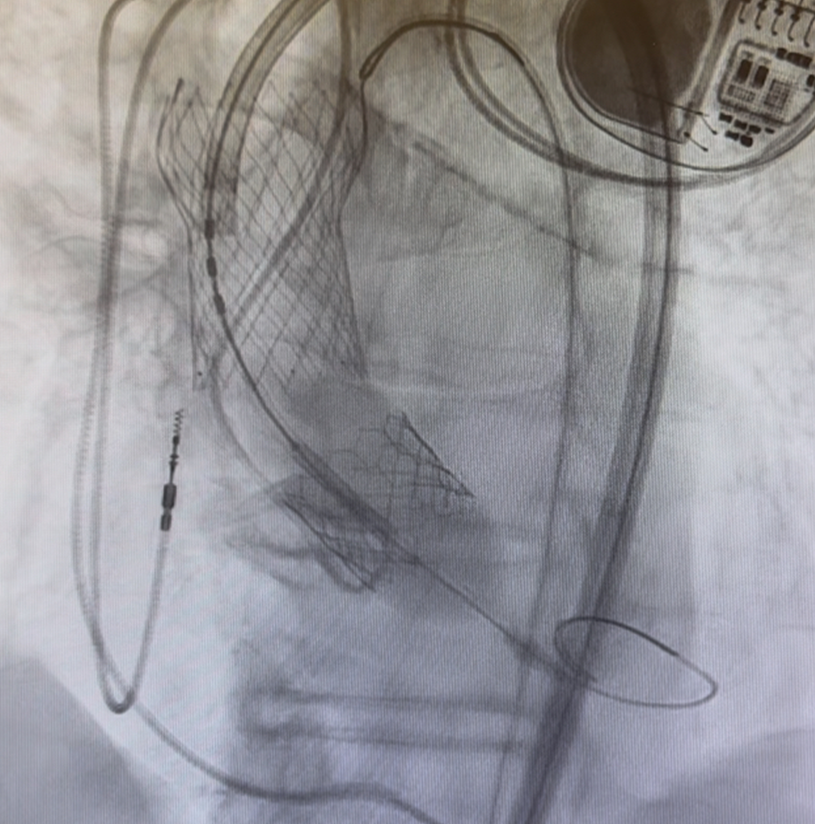

Embolized valve snared and parked in the ascending aorta

移位栓塞瓣膜被捕获并固定于升主动脉

结合患者血流动力学稳定、移位瓣膜已被捕获固定、跨平台瓣膜输送的技术可行性等因素,治疗团队最终决定采用第三种方案:选择23mm Sapien 3 Ultra Resilia球囊扩张式瓣膜,实施跨平台“瓣中瓣”植入。

23 mm Sapien Ultra Resilia valve advanced through the frame of dislodged valve and positioned across the native annulus

23 mm Sapien Ultra Resilia 瓣膜系统经移位瓣膜栓塞瓣架内推进,跨原生瓣环定位